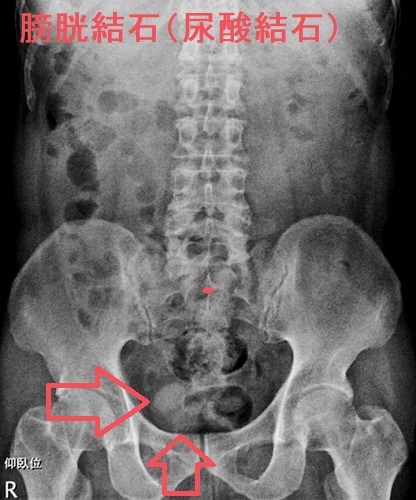

膀胱結石は成分別に

- 尿酸結石;赤レンガ色の結石。甲状腺機能亢進症/バセドウ病、甲状腺機能低下症/橋本病で高尿酸血症(高尿酸血症と甲状腺)

- シスチン結石

- ステロイド結石:ステロイドホルモンは骨破壊を増加、血中にカルシウムとリンが溶け出し、尿中に過剰に排泄され、結石が形成されます。副腎皮質ステロイドホルモンの1つコルチゾールが過剰に分泌されるクッシング症候群で(クッシング症候群の症状 )。

- 原発性副甲状腺機能亢進症による高カルシウム血症で(原発性副甲状腺機能亢進症の症状 )

があります。

膀胱結石は成因別に

- 腎臓の結石が膀胱まで落ちてきたもの

- 膀胱内で発生したもの;前立腺肥大症などによる排尿障害が原因で、膀胱内に結石の成分となる物質が停留し固まります。

膀胱結石の検査所見は

- 尿潜血陽性、尿沈渣で赤血球、白血球を認める

- 腹部超音波(エコー);結石が写る

- X線;結石が写る

- CT画像;結石が写る